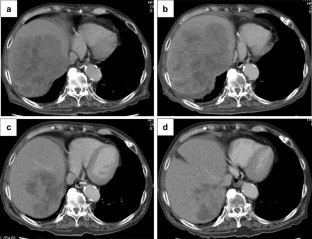

Immune checkpoint inhibitors may have different clinical effects compared with conventional anticancer drugs. An 85-year-old male received chemotherapy for recurrent gastric cancer. As liver metastasis progressed, nivolumab was introduced as a fourth line treatment. Progression of liver metastasis in size was observed in CT after 3 courses of nivolumab therapy. Nivolumab treatment was discontinued, because the general condition of the patient also worsened. However, his general condition improved as hepatobiliary enzyme levels, inflammatory response, and tumor markers improved. Liver metastasis was shrinking on the image, so we resumed nivolumab therapy. To the authors’ knowledge, this is the first case of pseudoprogression undergoing immunotherapy for gastric cancer. In this case, the antitumor effect was exhibited in a delayed manner and the tumor shrinkage was obtained.

Fig. 1

Fig. 2

Fig. 3